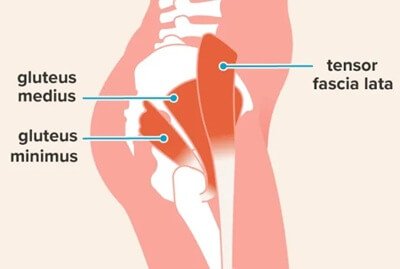

Hip abductor dysfunction refers to weakness, injury, or degeneration of the muscles responsible for stabilising the pelvis during walking and standing, particularly the gluteus medius and gluteus minimus. These muscles play a crucial role in maintaining balance and preventing the pelvis from tilting with each step. When the abductors are not functioning properly, patients may experience pain on the side of the hip, difficulty walking, limping (known as a Trendelenburg gait), or reduced stability.

The hip abductor muscles are a group of muscles located on the outer portion of your hip and upper thigh. Their main role is to stabilise the pelvis and move the leg away from the body, a motion known as abduction. They are essential for maintaining balance while walking, standing on one leg, or climbing stairs.

1. Gluteus Medius

- Located on the outer surface of the pelvis.

- The primary muscle responsible for hip abduction and stabilisation during walking.

- Prevents the pelvis from dropping on the opposite side when standing on one leg (Trendelenburg function).

2. Gluteus Minimus

- The smallest and deepest of the gluteal muscles, sitting beneath the gluteus medius.

- Assists in hip abduction and internal rotation.

- Works closely with the gluteus medius to maintain pelvic stability.

3. Tensor Fasciae Latae (TFL)

- A small muscle on the outer thigh that assists with abduction and internal rotation of the hip.

- Connects to the iliotibial (IT) band, contributing to hip and knee movement.